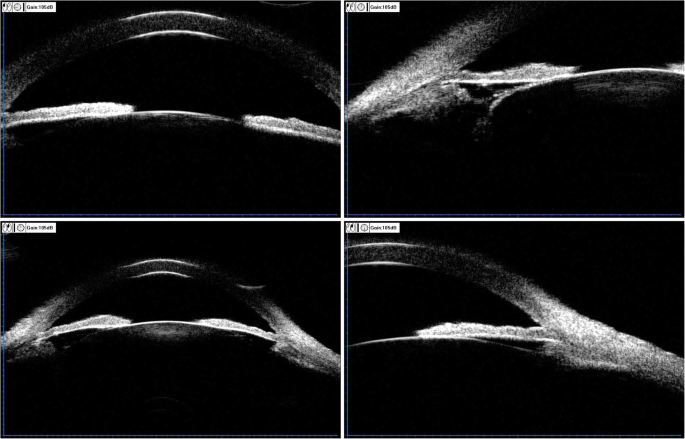

The patient is a 63-year-old male who was diagnosed with chronic angle-closure glaucoma and accepted UCP in another hospital on both eyes 4 months ago. We asked the hospital for the preoperative data of the patient. The visual acuity was 20/160 (OD) and 20/40 (OS), and the best-corrected visual acuity (BCVA) was preserved at 20/100 (OD) with + 0.50D/− 1.50D*10 and 20/25 (OS) with + 0.75D/− 1.50D*165. The patient presented with bilateral cataract (C2N2P1 OD, C2N2P1 OS) according to Lens Opacities Classification System III (LOCS III). The optic discs of both eyes were pale with C/D = 0.9 (OD) and C/D = 0.8 (OS), respectively. The ultrasound biomicroscope (UBM) data were as follows: The iris of both eyes was swollen and the anterior chambers were narrow. In the right eye, the vertical anterior chamber depth was 2.24 mm and the corresponding sulcus-to-sulcus distance was 12.11 mm, and the horizontal anterior chamber depth was 2.28 mm with the corresponding sulcus-to-sulcus distance of 11.80 mm. In the left eye, the vertical anterior chamber depth was 2.26 mm and the corresponding sulcus-to-sulcus distance was 11.98 mm, and the horizontal anterior chamber depth was 2.24 mm with the corresponding sulcus-to-sulcus distance of 11.90 mm. Visual field examination showed that the right eye had a tubular visual field and the left eye had a peripheral visual field defect. Under the situation of using three kinds of anti-glaucoma drugs (methazolamide, carteolol hydrochloride, and brinzolamide), the baseline intraocular pressure (IOP) was 30 mmHg (OD) and 31 mmHg (OS), respectively. The preoperative anterior segment image (Fig. 1) showed that pupils of both eyes were regular circular and the depth of the anterior chamber was normal. The preoperative UBM image (Fig. 2) presented that the anterior chamber angle of both eyes was closed, the lens position was normal without deviation, and the anterior capsule was smooth without adhesion.

Three months after the UCP treatment, under the situation of using three kinds of anti-glaucoma drugs (methazolamide, carteolol hydrochloride, and brinzolamide), the IOP value of the patient fluctuated in the range of 22–30 mmHg and the visual acuity decreased to 20/250 (OD) and 20/80 (OS). It was found that the BCVA was preserved at 20/40 (OD) with − 1.25 DC*35 and 20/32 (OS) with + 2.50DS/− 3.00 DC*155. After the UCP treatment, the image of the anterior segment (Fig. 3) exhibited that both pupils were vertical elliptical, of which the diameters were 3.0 mm*5.0 mm (OD) and 3.0 mm*4.0 mm (OS), respectively. Also, local iris atrophy on the subnasal of the left eye was observed. The central anterior chamber depth was about 2.5 corneal thickness (CT). The left eye had a peripheral anterior chamber depth of about 1/4 CT while the peripheral anterior chamber depth of the right eye varied greatly, which indicates an angle adhesion. The patient presented with bilateral cataract (C2N3P1 OD, C2N2P1 OS) according to LOCS III. The UBM image (Fig. 4) showed that both pupils were deformed, in which the left eye had an irregular superior suspensory ligament and the lens of the right eye deviated. The central anterior chamber depth was about 2.32 mm (OD) and 2.25 mm (OS), respectively. As shown in the image, the anterior chamber angle was closed in all directions while the ciliary body displaced forward to the root of the iris in both eyes. Both lenses showed enhanced echo. It is seen that there exists adhesion in the anterior capsule periphery of both lenses and the lens position of the right eye deviates.